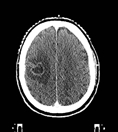

転移性脳腫瘍に対する定位放射線治療例です。

右図:治療後の状態です。丸く白く見える部分がなくなり、腫瘍が消失しています。